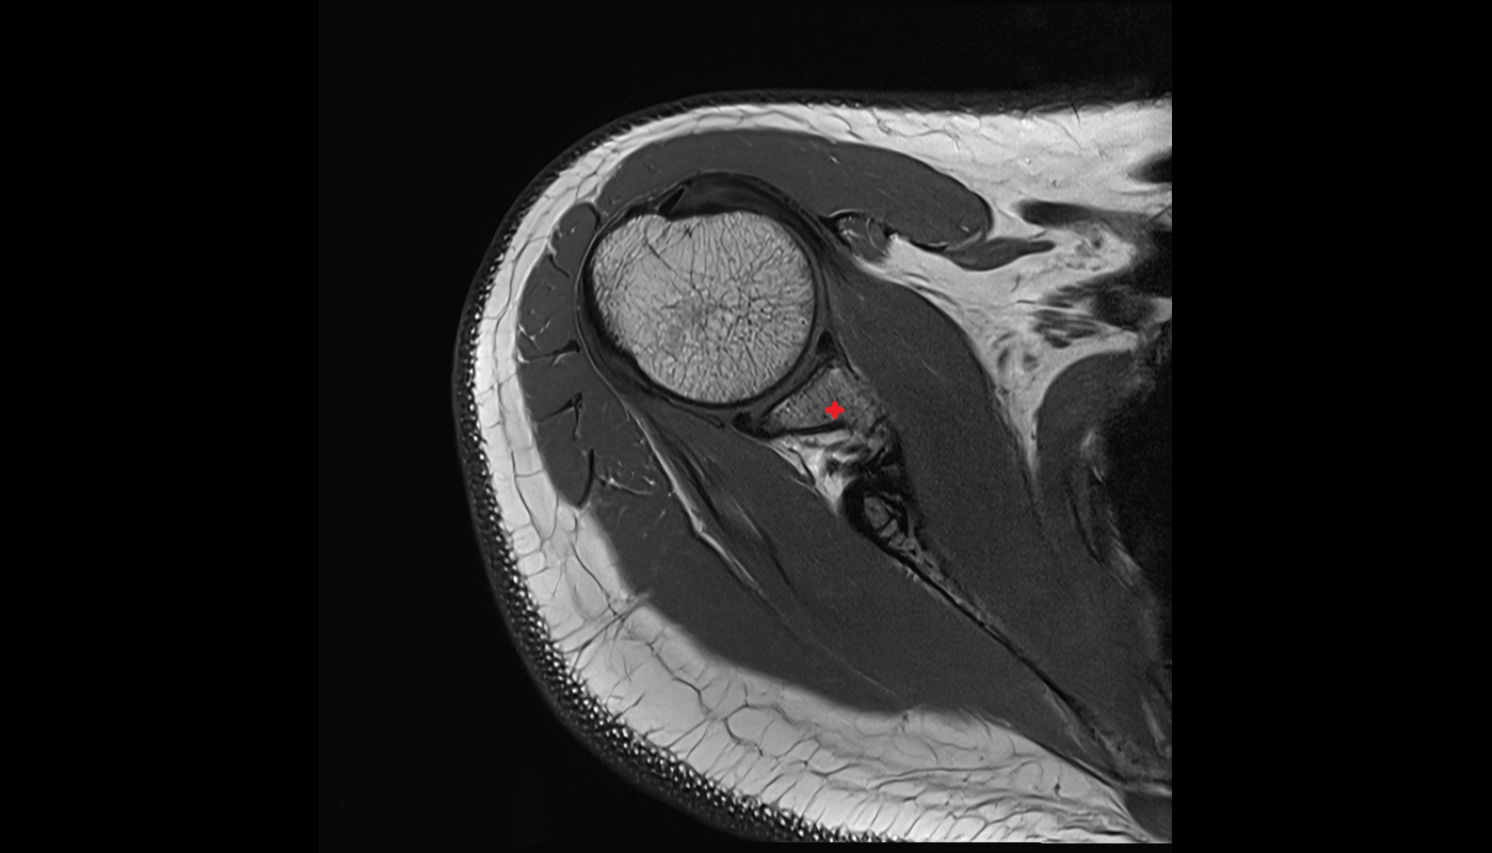

- Shoulder joint (glenohumeral joint)

- Glenoid labrum

- Supraspinatus tendon

- Long head of biceps tendon

- Glenohumeral joint capsule

- Glenoid fossa

- Head of humerus